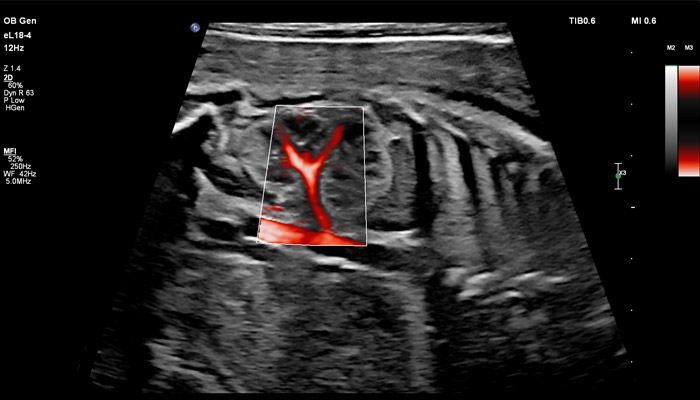

В случае аномалий позвоночника, оценка ануса важна, чтобы исключить аноректальные пороки развития, которые могут быть частью более широкой группы аномалий, известных как VACTERL (аномалии позвоночника, атрезия ануса, пороки сердца, трахеопищеводный свищ, аномалии почек, дефекты лучевой кости). Исследования в США показали, что очень высокое качество изображений еL18-4 повышают уверенность клиницистов в исключении аноректальной аномалии плода. Точная оценка состояния плаценты важна при определении сроков родоразрешения, а также при планировании хирургических вмешательств. Изображения показывают нормальный миометрий и четкую границу с плацентой. С визуализацией микрокровотока (MFI) хорошо представлены дугообразные артерии матери, спиральные артерии, а также ветвящиеся ворсинчатые артерии, что подтверждает нормально развитую сосудистую систему. Клинические исследования, проведенные экспертами детской больницы штата Аризона (США) во главе с Д-ром Льюсом Гонкалвсом с целью определения наличия нормальной сосудистой структуры плаценты при подозрении на ее патологию, показали, что инновационная технология сверхширокополосной PureWave матрицы датчика eL18-4 способна изменить привычный способ, которым врачи интерпретируют нормальный и аномальный сосудистый поток в плаценте.

Линейный матричный датчик eL18-4 поддерживает режим высокочувствительной визуализации кровотока (Philips MicroFlow Imaging), новый запатентованный метод, который обеспечивает инновационный подход к оценке сосудистого русла. Визуализация MicroFlow преодолевает многие барьеры, связанные с традиционными методами обнаружения кровотока в малых сосудах, обеспечивая высокое разрешение при минимальных артефактах. Метод MicroFlow Imaging поддерживает высокую частоту кадров и качество изображения, применяет инновационные методы сокращения артефактов. Варианты вычитания 2D-изображений, смешивания и параллельного отображения обеспечивают превосходную визуализацию в различных клинических случаях.